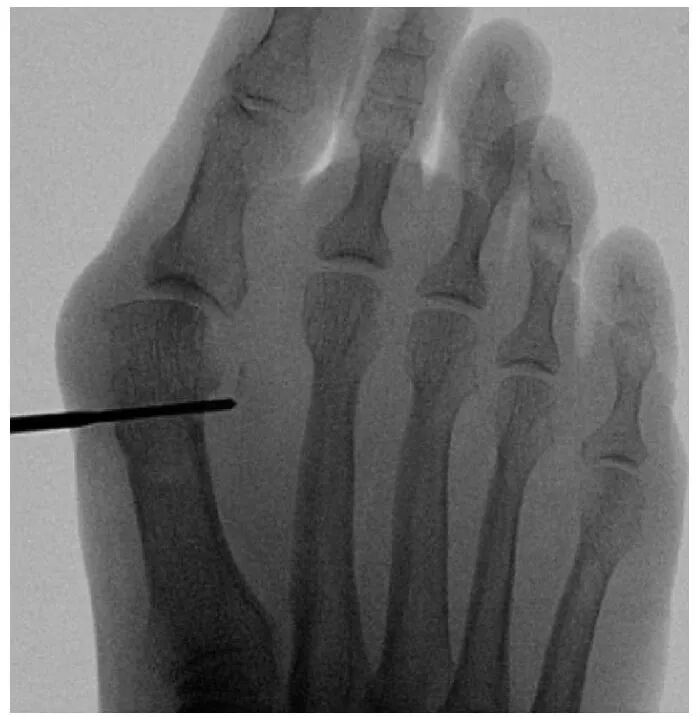

截骨完成后,将弯曲的骨膜剥离器插入截骨部位,以平移第一跖骨头。通过近节趾骨基部内侧的3毫米切口进行额外的Akin截骨术。使用一枚2毫米克氏针通过截骨端沿拇趾内侧软组织向远端穿过,从趾尖的跖内侧穿出。然后将克氏针逆行插入第一跖骨的髓管。

在最终确认拇外翻矫形满意后关闭伤口。应用绷带保护手术伤口和克氏针。术后一天允许患者根据耐受情况完全负重,使用前足减压的术后鞋。六周后患者可以根据耐受情况开始穿常规鞋履。